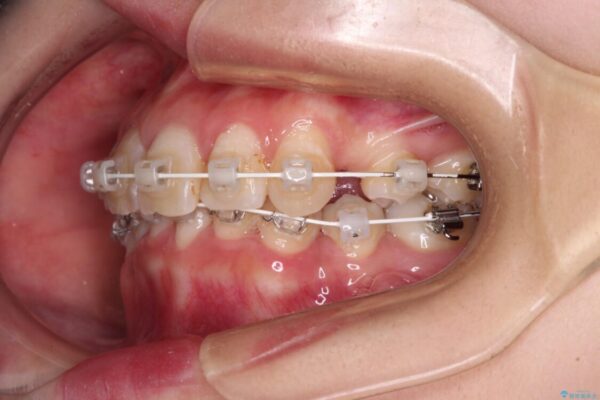

治療途中

• デコボコと深い咬み合わせ ワイヤー装置での抜歯矯正 治療途中画像

咬み合わせが深く、そのままでは上顎の抜歯スペースが閉じきらない可能性があったため、治療初期から深い咬み合わせを改善させるように試みました。

実際にはなかなか改善されず、当初予定よりも治療期間がやや長期化してしまいました。